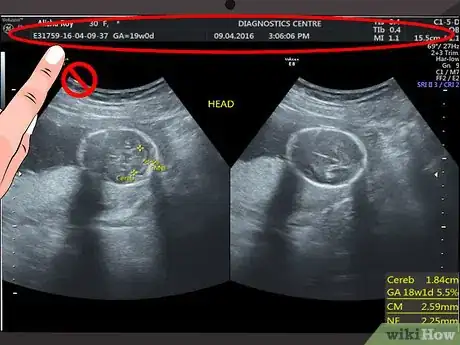

1Disregard the text and numbers at the top of your scan. Most hospitals and ultrasound centers use this space to include details like your name, hospital reference number, or ultrasound machine settings. Since this information does not have anything to do with what you see on the ultrasound image, you can ignore this information.[1]

3Determine your baby’s sex. At around 18 to 20 weeks, you will have an ultrasound to check your baby’s development, identify any problems, and possibly even identify the sex]] of your baby. It’s important to remember that it is not always possible to determine the sex of your baby at this stage and you won’t know for sure until your baby is born.[9]

- To determine the sex of your baby, the ultrasound technician or obstetrician will look for a penis or three lines that represent the labia. Keep in mind that this method of determining the sex of your baby is not 100% accurate. A visual effect may create or obscure the image of a penis on an ultrasound.